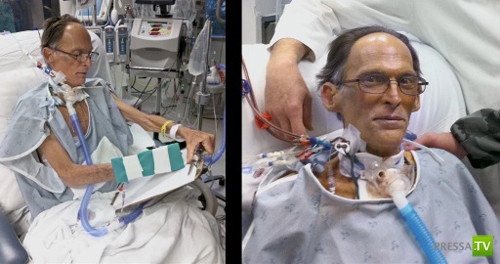

Докторам Билли Кон и Бад Фрейзер из Техасского Института Хирургии Сердца пришла идея заменить человеческое сердце специальным насосом, который позволял крови циркулировать по телу при отсутствии пульса. Они не только придумали и построили это устройство, но и успешно протестировали его на 50-ти телятах. Они познакомились с 55-летним Крэйгом Льюисом (Craig Lewis), которому осталось жить совсем немного. Когда они предложили ему и его семье поучаствовать в этом научном эксперименте и заменить сердце мужчины на новое устройство, жена безнадежно больного Крэйга дала свое согласие.

Доктора удалили сердце пациента из груди, а вместо него поставили данное революционное устройство. Операция прошла успешно. В течении дня после операции Крэйг смог уже говорить и чувствовал себя хорошо.

Таким образом, благодаря этим двум докторам-гениям Крэйг стал первым в мире человеком без сердца, также у него не было пульса!

Докторам Билли Кон и Бад Фрейзер из Техасского Института Хирургии Сердца пришла идея заменить человеческое сердце специальным насосом, который позволял крови циркулировать по телу при отсутствии пульса. Они не только придумали и построили это устройство, но и успешно протестировали его на 50-ти телятах. Они познакомились с 55-летним Крэйгом Льюисом (Craig Lewis), которому осталось жить совсем немного. Когда они предложили ему и его семье поучаствовать в этом научном эксперименте и заменить сердце мужчины на новое устройство, жена безнадежно больного Крэйга дала свое согласие.

Доктора удалили сердце пациента из груди, а вместо него поставили данное революционное устройство. Операция прошла успешно. В течении дня после операции Крэйг смог уже говорить и чувствовал себя хорошо.

Таким образом, благодаря этим двум докторам-гениям Крэйг стал первым в мире человеком без сердца, также у него не было пульса!